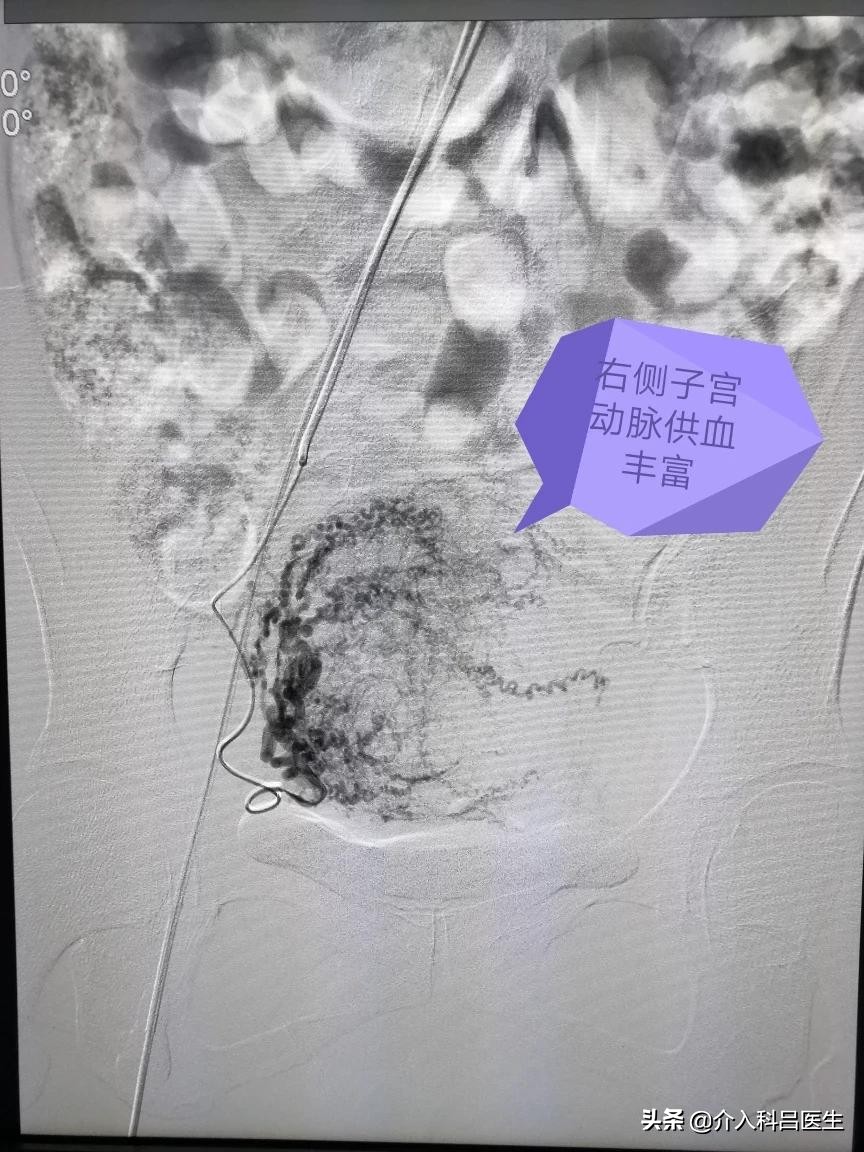

打眼一看就是典型的南方人面孔,可是脸色苍白,典型的贫血貌,心率明显快,血压有点低,都是肌瘤贫血引起的,双侧子宫动脉供血很丰富,栓塞很彻底,只留下子宫动脉主干,肌瘤缺血坏死萎缩吸收,子宫由于还有其他血管供血,不至于坏死,大概半年后子宫就能够恢复正常了。

术前